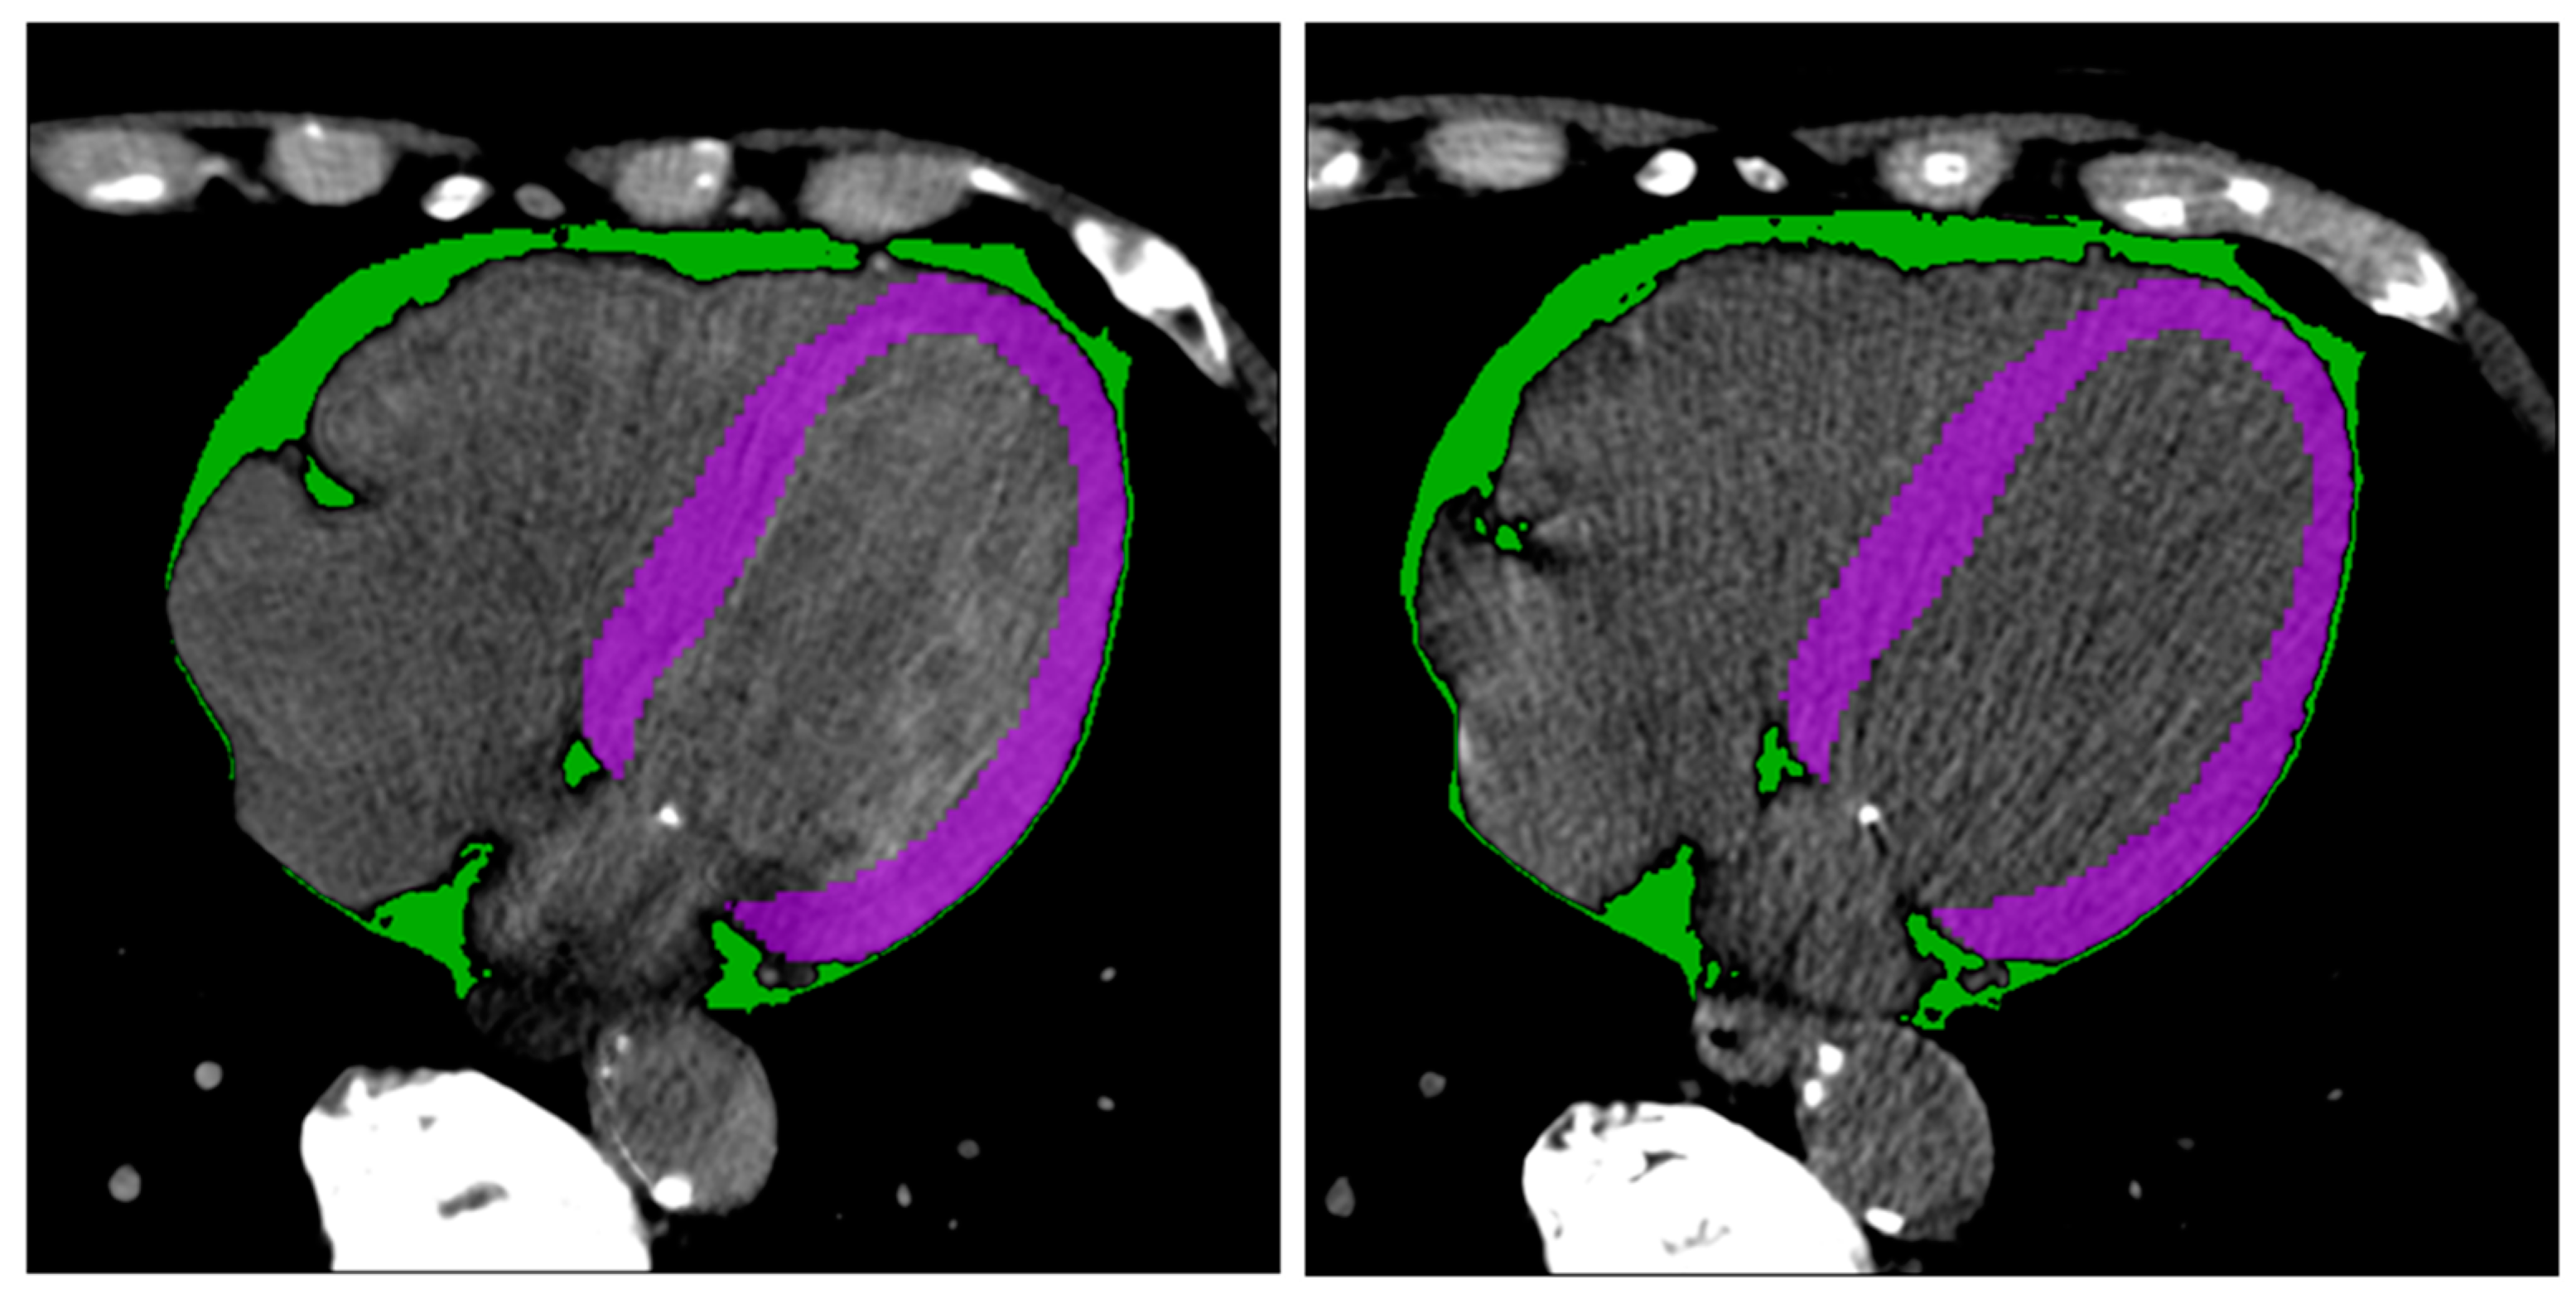

Figure 3 shows two example masks of the myocardium and epicardial fat in intra-patient TNC and VNC images. The number of radiomics features extracted in each reconstruction for every anatomical structure is 105. The complete list of extracted features is available in Figure 4 (x-axis). ICC values computed for VNC and TNC reconstructions of myocardium and epicardial fat are available in Figure 4 and Figure 5. The values of the ICC coefficients are ordered in a descending fashion to better comprehend which features are more correlated (i.e., remain more stable) between VNC and TNC acquisitions. In each Figure, the blue square identifies the related ICC value, which is also reported, and the extremities of vertical lines crossing each square represent the lower and upper bounds. Figure 4 presents the ICC values computed for the features extracted from the myocardium. Similarly, Figure 5 displays the ordered ICC values computed for the features extracted for the epicardial fat.

Figure 3.

Segmentation results. Segmentation of myocardium (in green) and epicardial fat (in purple) in intra-patient TNC and VNC images (first and second subfigure, respectively). Figures are visualized with window center 97 and window width equal to 215.